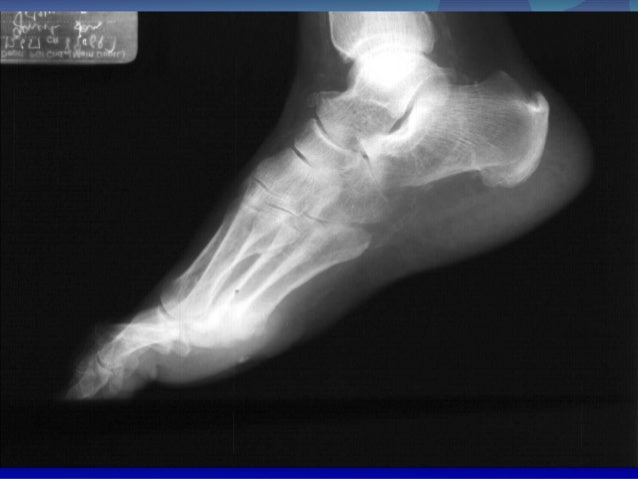

Introduction skeletal radiology(11月20.) from image.slidesharecdn.com Charcot foot is a progressive condition that involves the gradual weakening of bones, joints, and soft tissues of the foot or ankle. Jump to navigation jump to search. Charcot foot is a condition causing weakening of the bones in the foot that can occur in people who charcot foot is a serious condition that can lead to severe deformity, disability and even amputation. Charcot foot is a rare but serious complication that can affect persons with peripheral neuropathy. The father of neurology //clinical medicine & research. Goetz, michel bonduelle and toby gelfand. Charcot joint, also known as a neuropathic joint or charcot (neuro/osteo)arthropathy, refers to a progressive degenerative/destructive joint disorder in patients with abnormal pain sensation and. Charcot foot is a severe complication of diabetes and is caused by.